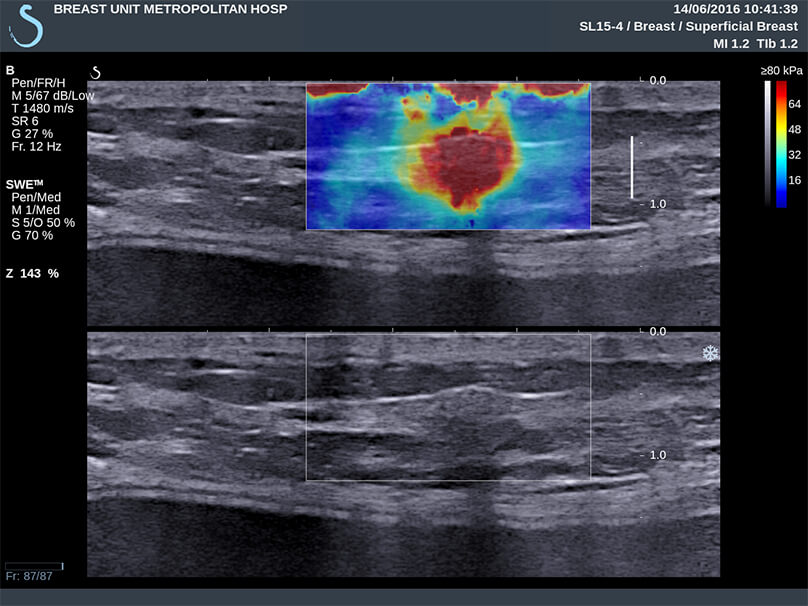

Περιπτώσεις ευρημάτων στο υπερηχογράφημα που μελετήθηκαν περαιτέρω με τεχνική ελαστογραφίας η οποία κατέγραψε μαλακό υπόστρωμα (μπλε χρώμα), που, στις περισσότερες περιπτώσεις, αφορά σε καλοήθεις καταστάσεις του μαστού, απομακρύνοντας ουσιαστικά το ενδεχόμενο της κακοήθειας.